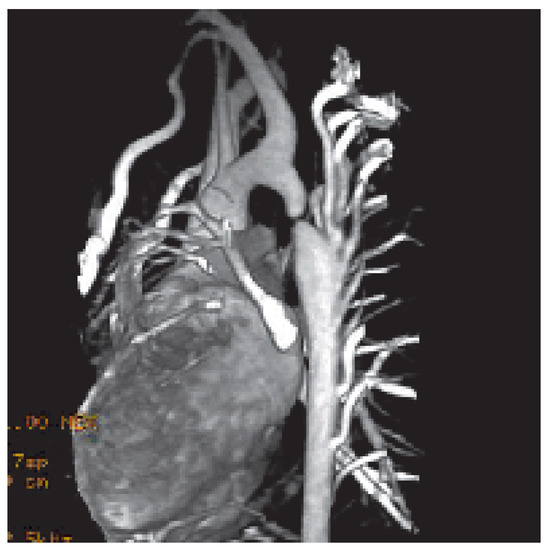

Der hochgradige Verdacht auf eine Aortenisthmusstenose (AIS) wurde durch die MRT bestätigt: hier fand sich eine subatretische, kurzstreckige AIS mit ausgeprägter Kollateralisierung (Figure 2).

Figure 2.

Dreidimensionale Rekonstruktion der MR-Angiographie. Eine hochgradige Stenose zeigt sich im Isthmusbereich. Ausgeprägter Umgehungskreislauf durch die Paravertebralarterien und beide Aa. mammariae.